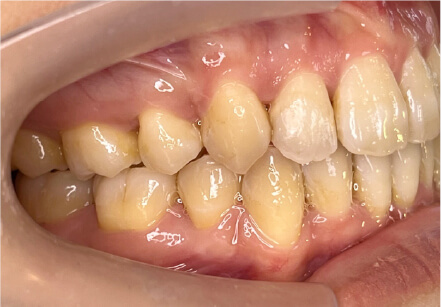

叢生の症例

10歳

/

女性

相談内容

スペース不足

カウンセリング・診断結果

myoからの移行。スペース不足のためインビザライン開始。

治療内容・方法

全額アライナー矯正

術後の経過・現在の様子

クリアライナー使用

治療のリスク

痛み・歯根吸収・歯肉退縮・虫歯・後戻り

費用・治療期間

(インビザのみ)385,000円、1年2ヶ月 + myo3年4ヶ月

トレーニングなど